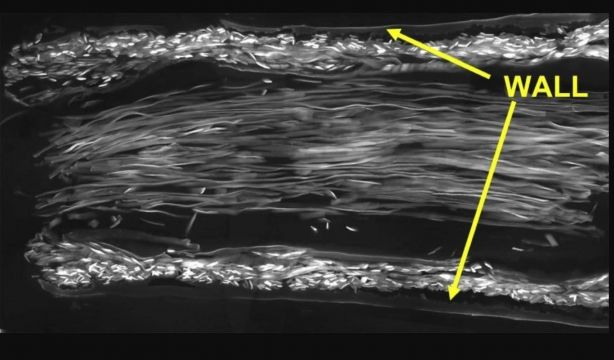

En este estudio, el equipo desarrolló una nueva guía nerviosa con dos tipos de seda natural: la pared se fabricó con seda producida por gusanos de seda y el interior con fibras de seda de dragalinas de telarañas doradas. Se probaron en ratas a las que se les había cortado el nervio ciático derecho, creando un espacio de 10 mm -una distancia significativa para una rata-. Descubrieron que los nervios dañados se habían adaptado a las nuevas guías y habían crecido a lo largo de los hilos de seda hasta que los extremos cortados se reconectaron con éxito.

Para analizar el proceso de curación en detalle utilizaron técnicas de microscopía avanzadas. Esto mostró que los tubos de seda tenían una estructura altamente porosa, una característica esencial para la regeneración nerviosa, ya que permite el intercambio de nutrientes y materiales de desecho.

Además, las células de Schwann -los impulsores clave de la regeneración de los nervios periféricos- se adhirieron fuertemente, tanto a las paredes del tubo como a las fibras de seda de la línea de arrastre, y migraron a una velocidad notable (más de 1,1 mm al día). También se ha demostrado que ambos tipos de seda desempeñaban un papel importante en la regeneración nerviosa: cuando las lesiones nerviosas se repararon utilizando tubos de seda vacíos -sin relleno de seda de araña-, las fibras nerviosas crecieron más lentamente y menos organizadas.